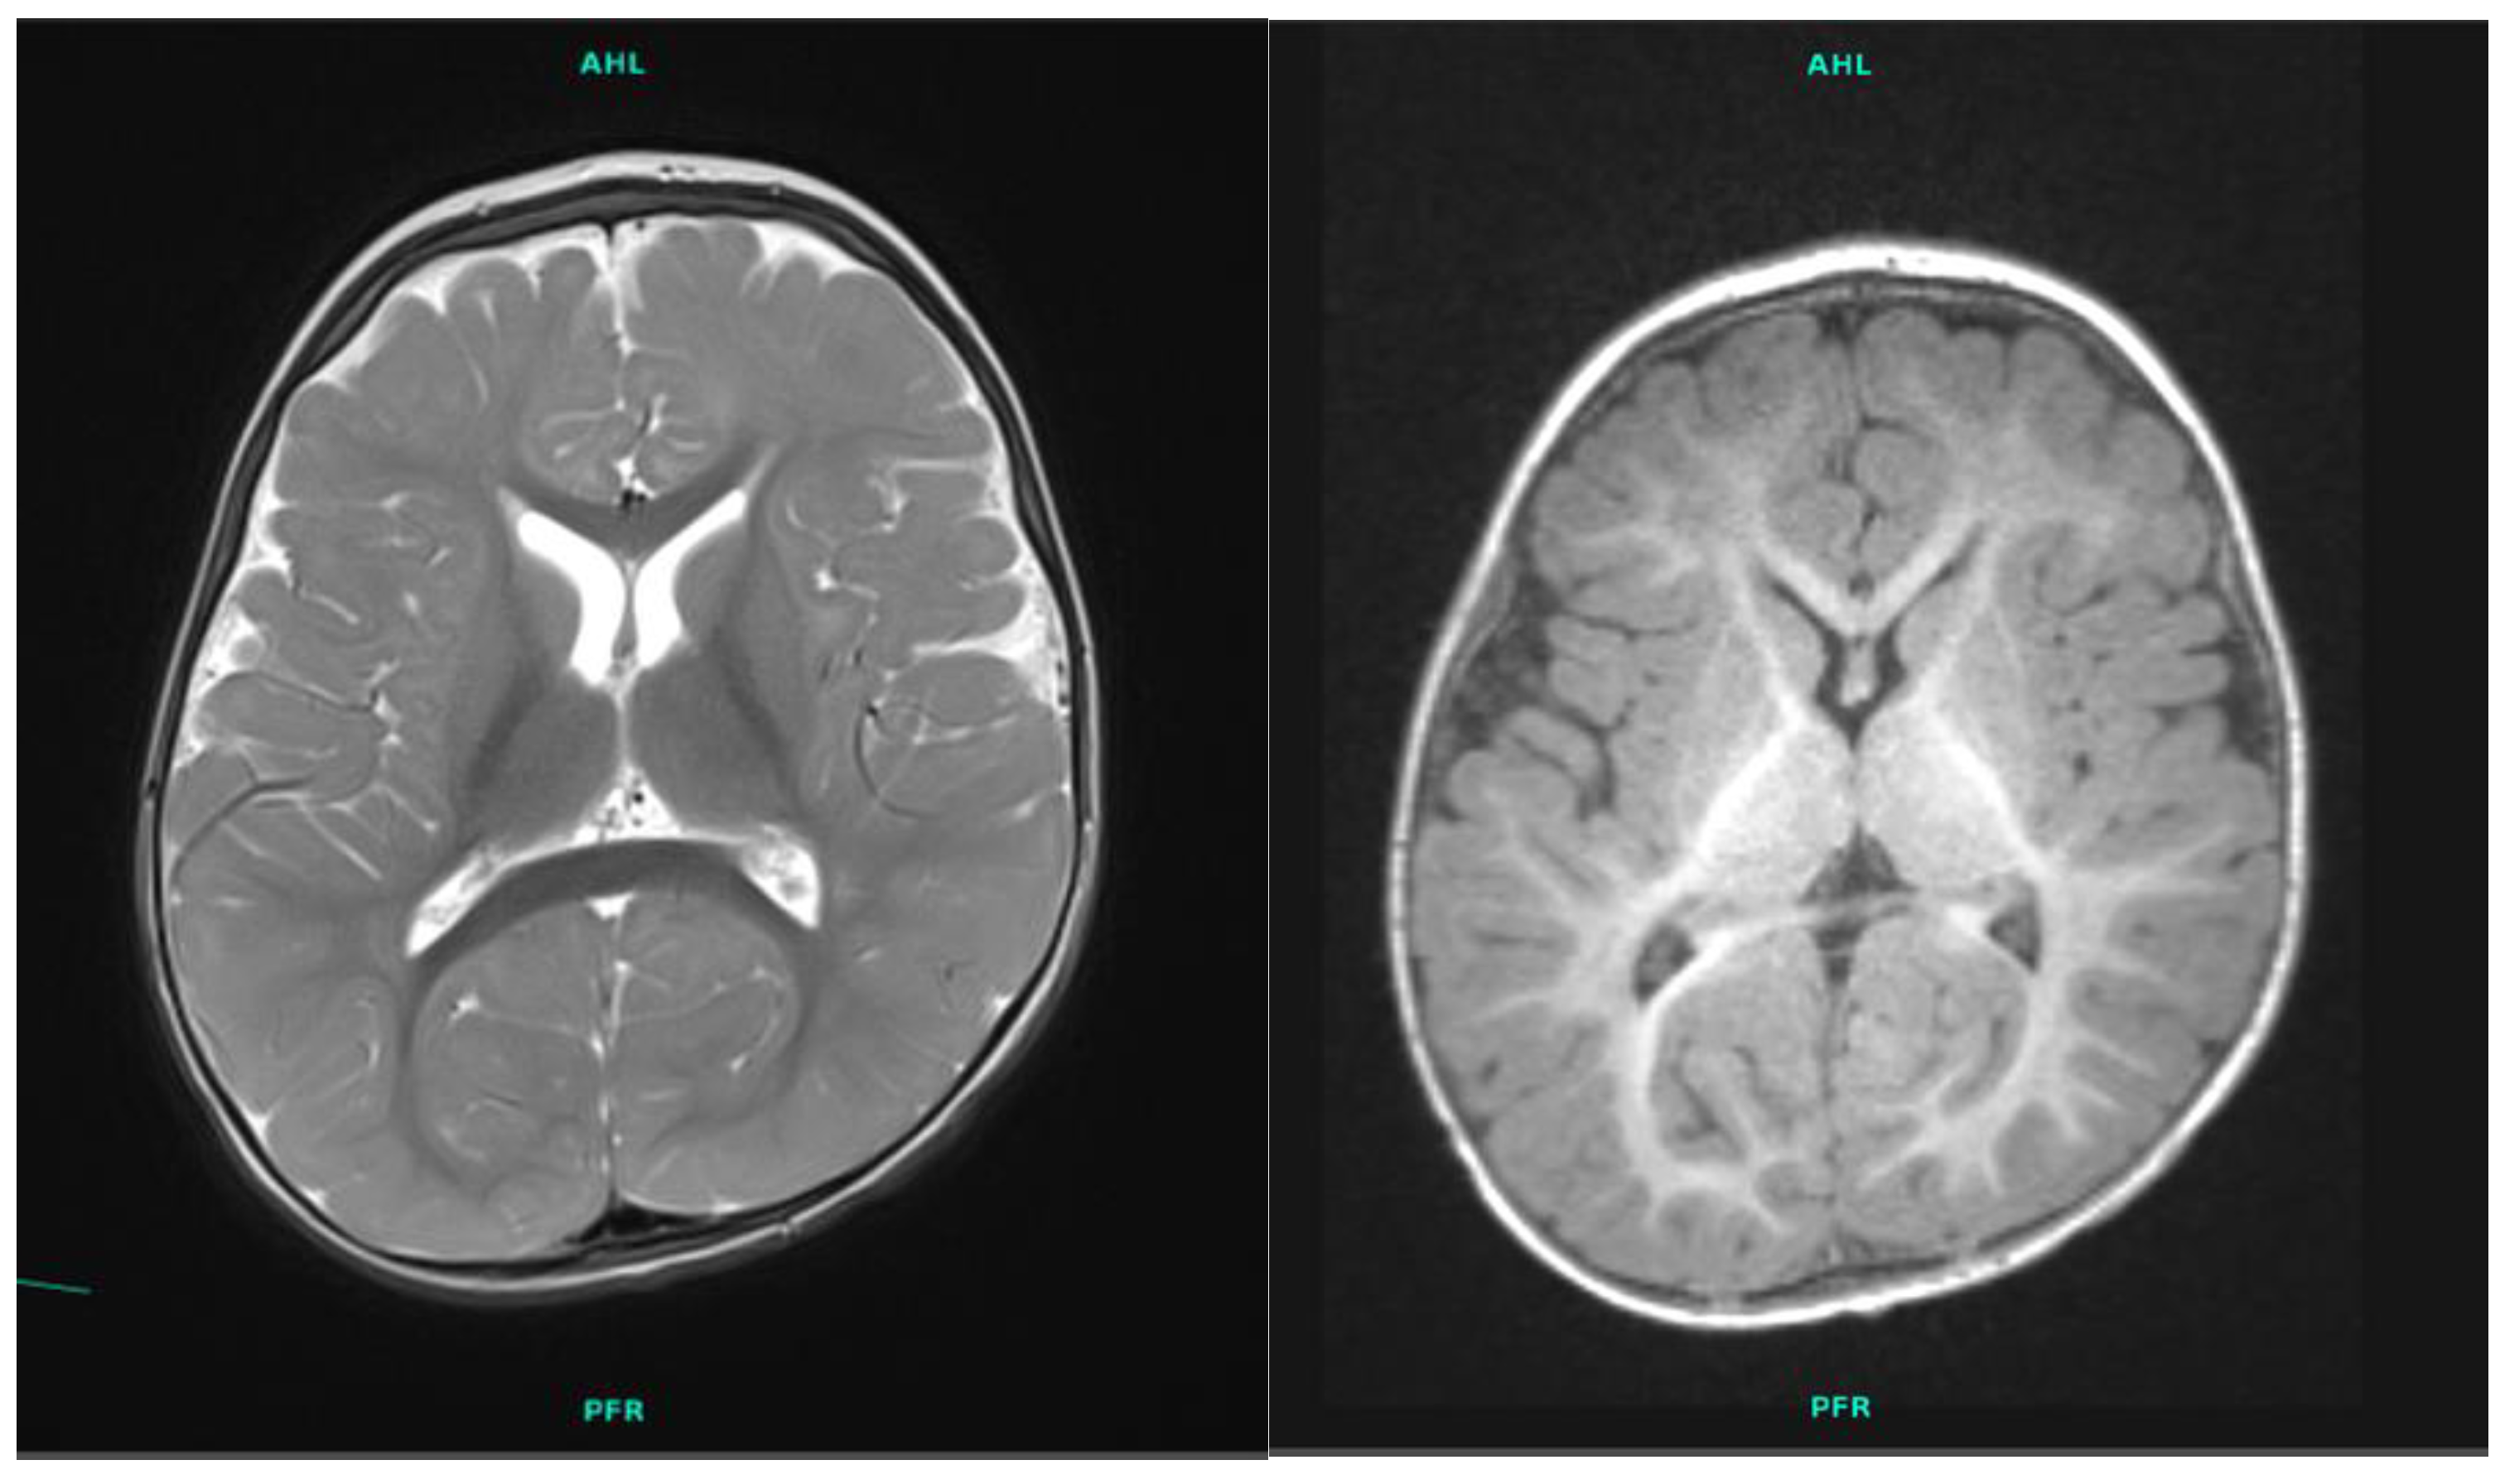

| Brain MRI | smaller basal ganglia and cerebral atrophy | N/A |